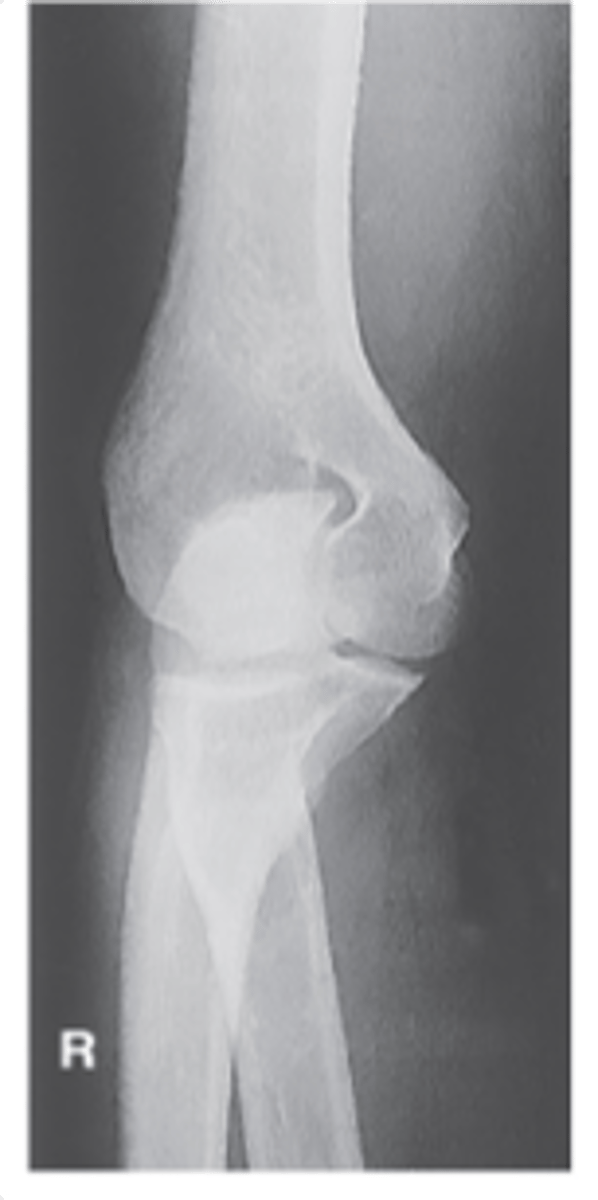

AP Lateral (External) Oblique Elbow

AP medial (internal) oblique elbow